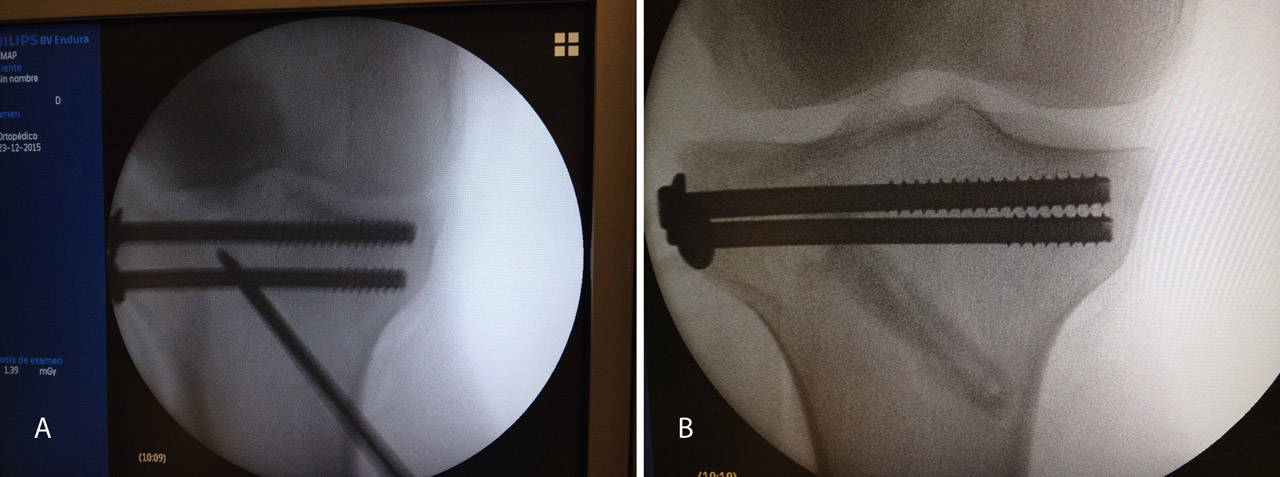

A raíz del artículo de Caspari(11), comenzamos a utilizar la artroscopia en nuestro medio en las fracturas de meseta tibial Schatzker de tipo II, en las que realizábamos la elevación del fragmento hundido mediante el uso de impactores desde la zona diafisometafisaria de la tibia, relleno del defecto con cemento biocompatible y fijación con tornillos canulados con arandela. Publicamos nuestra experiencia en los Cuadernos de Artroscopia en 1998(12)(Figuras 2 y 3).

Figura 1. Visión del cirujano de la reducción articular en una fractura de meseta tibial.

Figura 2. Técnica quirúrgica en fracturas de meseta tibial asistidas por artroscopia: elevación del fragmento hundido mediante impactor.

Figura 3. Técnica quirúrgica en fracturas de meseta tibial asistidas por artroscopia: relleno con cemento biocompatible y fijación con tornillos canulados de esponjosa.